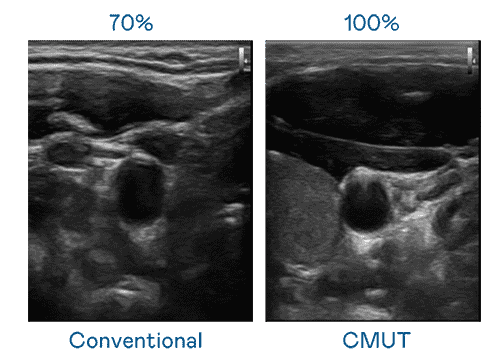

CMUT 技术是一种用电容式微机电元件来产生超音波讯号的技术。。与传统 PZT 压电式技术相比,,CMUT 频宽增加 30%,,更宽频的超音波讯号让影像解析度大幅提升,,,,是实现高影像品质医疗超音波扫描、、促进精准医疗发展的关键技术。。

大频宽带来超清晰影像

超音波影像的解析度高低,,,,首先取决于探头能发出的讯号频宽。。PG国际 CMUT 可提供高清晰的超音波讯号,,提供高频宽、、、高灵敏度、、、影像纹理细节更高的超音波影像,,协助医护人员缩短影像判读时间及利用精准的医疗影像进行诊断。。。